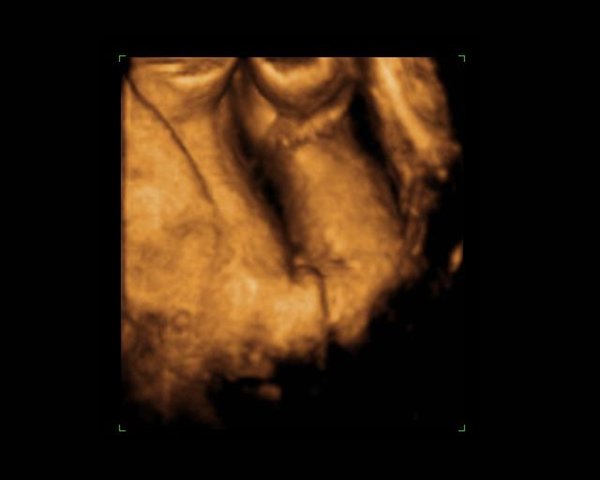

Dernæst havde vi bestilt tid til en privat 3d/4dscanning på scanningsklinikken i København, men den første gang lå hun med hænderne foran ansigtet, så vi blev tilbudt en ekstra gratis.. Det samme skete så anden gang igen og så var de så søde at vi fik en tredje gang, og så kunne vi endelig se hendes smukke ansigt